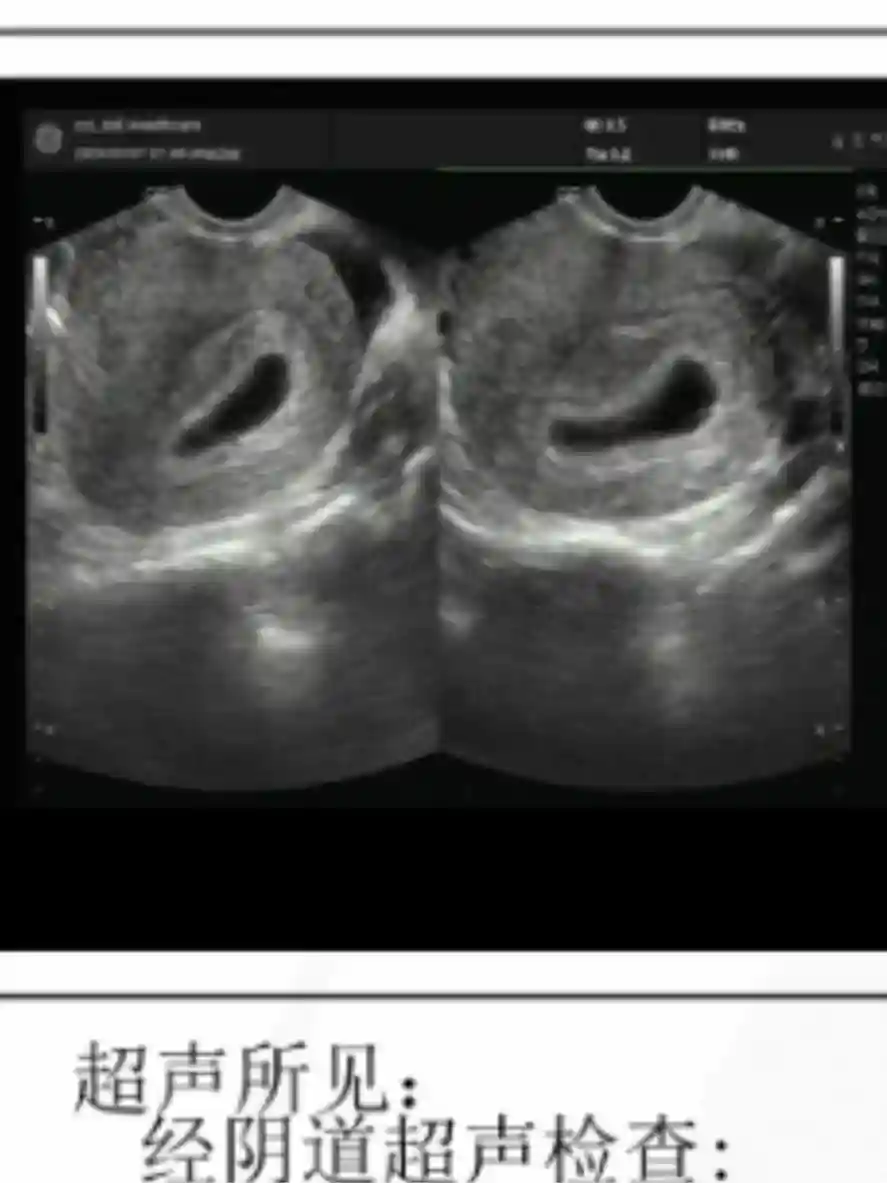

2️⃣孕囊形状不准❌:完全长条茄子🍆(图3)